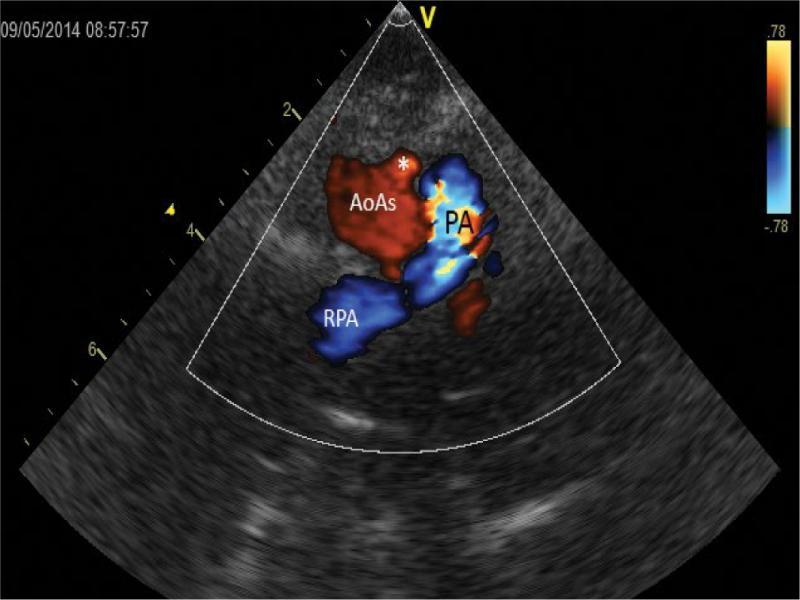

Systole. A round cross-section of the ascending aorta (AoAs) filled with red, and the pulmonary trunk (PA) and the right pulmonary artery (RPA) – blue color. A bulge corresponding to the origin of the left common carotid artery (*) is present in the anterior left contour of the ascending aorta (*)

Echocardiographic diagnosis revealed situs solitus, compatible venoatrial and atrioventricular junctions; aortic dextroposition (40–50%) over a large (approx. 12 mm) perimembranous ventricular septal defect (VSD). There was a bidirectional ventricular septal defect shunt, with left-to-right predominance. Right-sided aortic arch. Due to difficult anatomical conditions, no conclusion was made regarding the morphology of arterial branches of the arch (Fig. 2, Fig. 3, Fig. 4. Fig. 5, Fig. 6, Fig. 7 and Fig. 8). Figure 2, Fig. 3, Fig. 4 and Fig. 5 show a series of upper mediastinal vessel sections in a plane similar to transverse plane – horizontal.